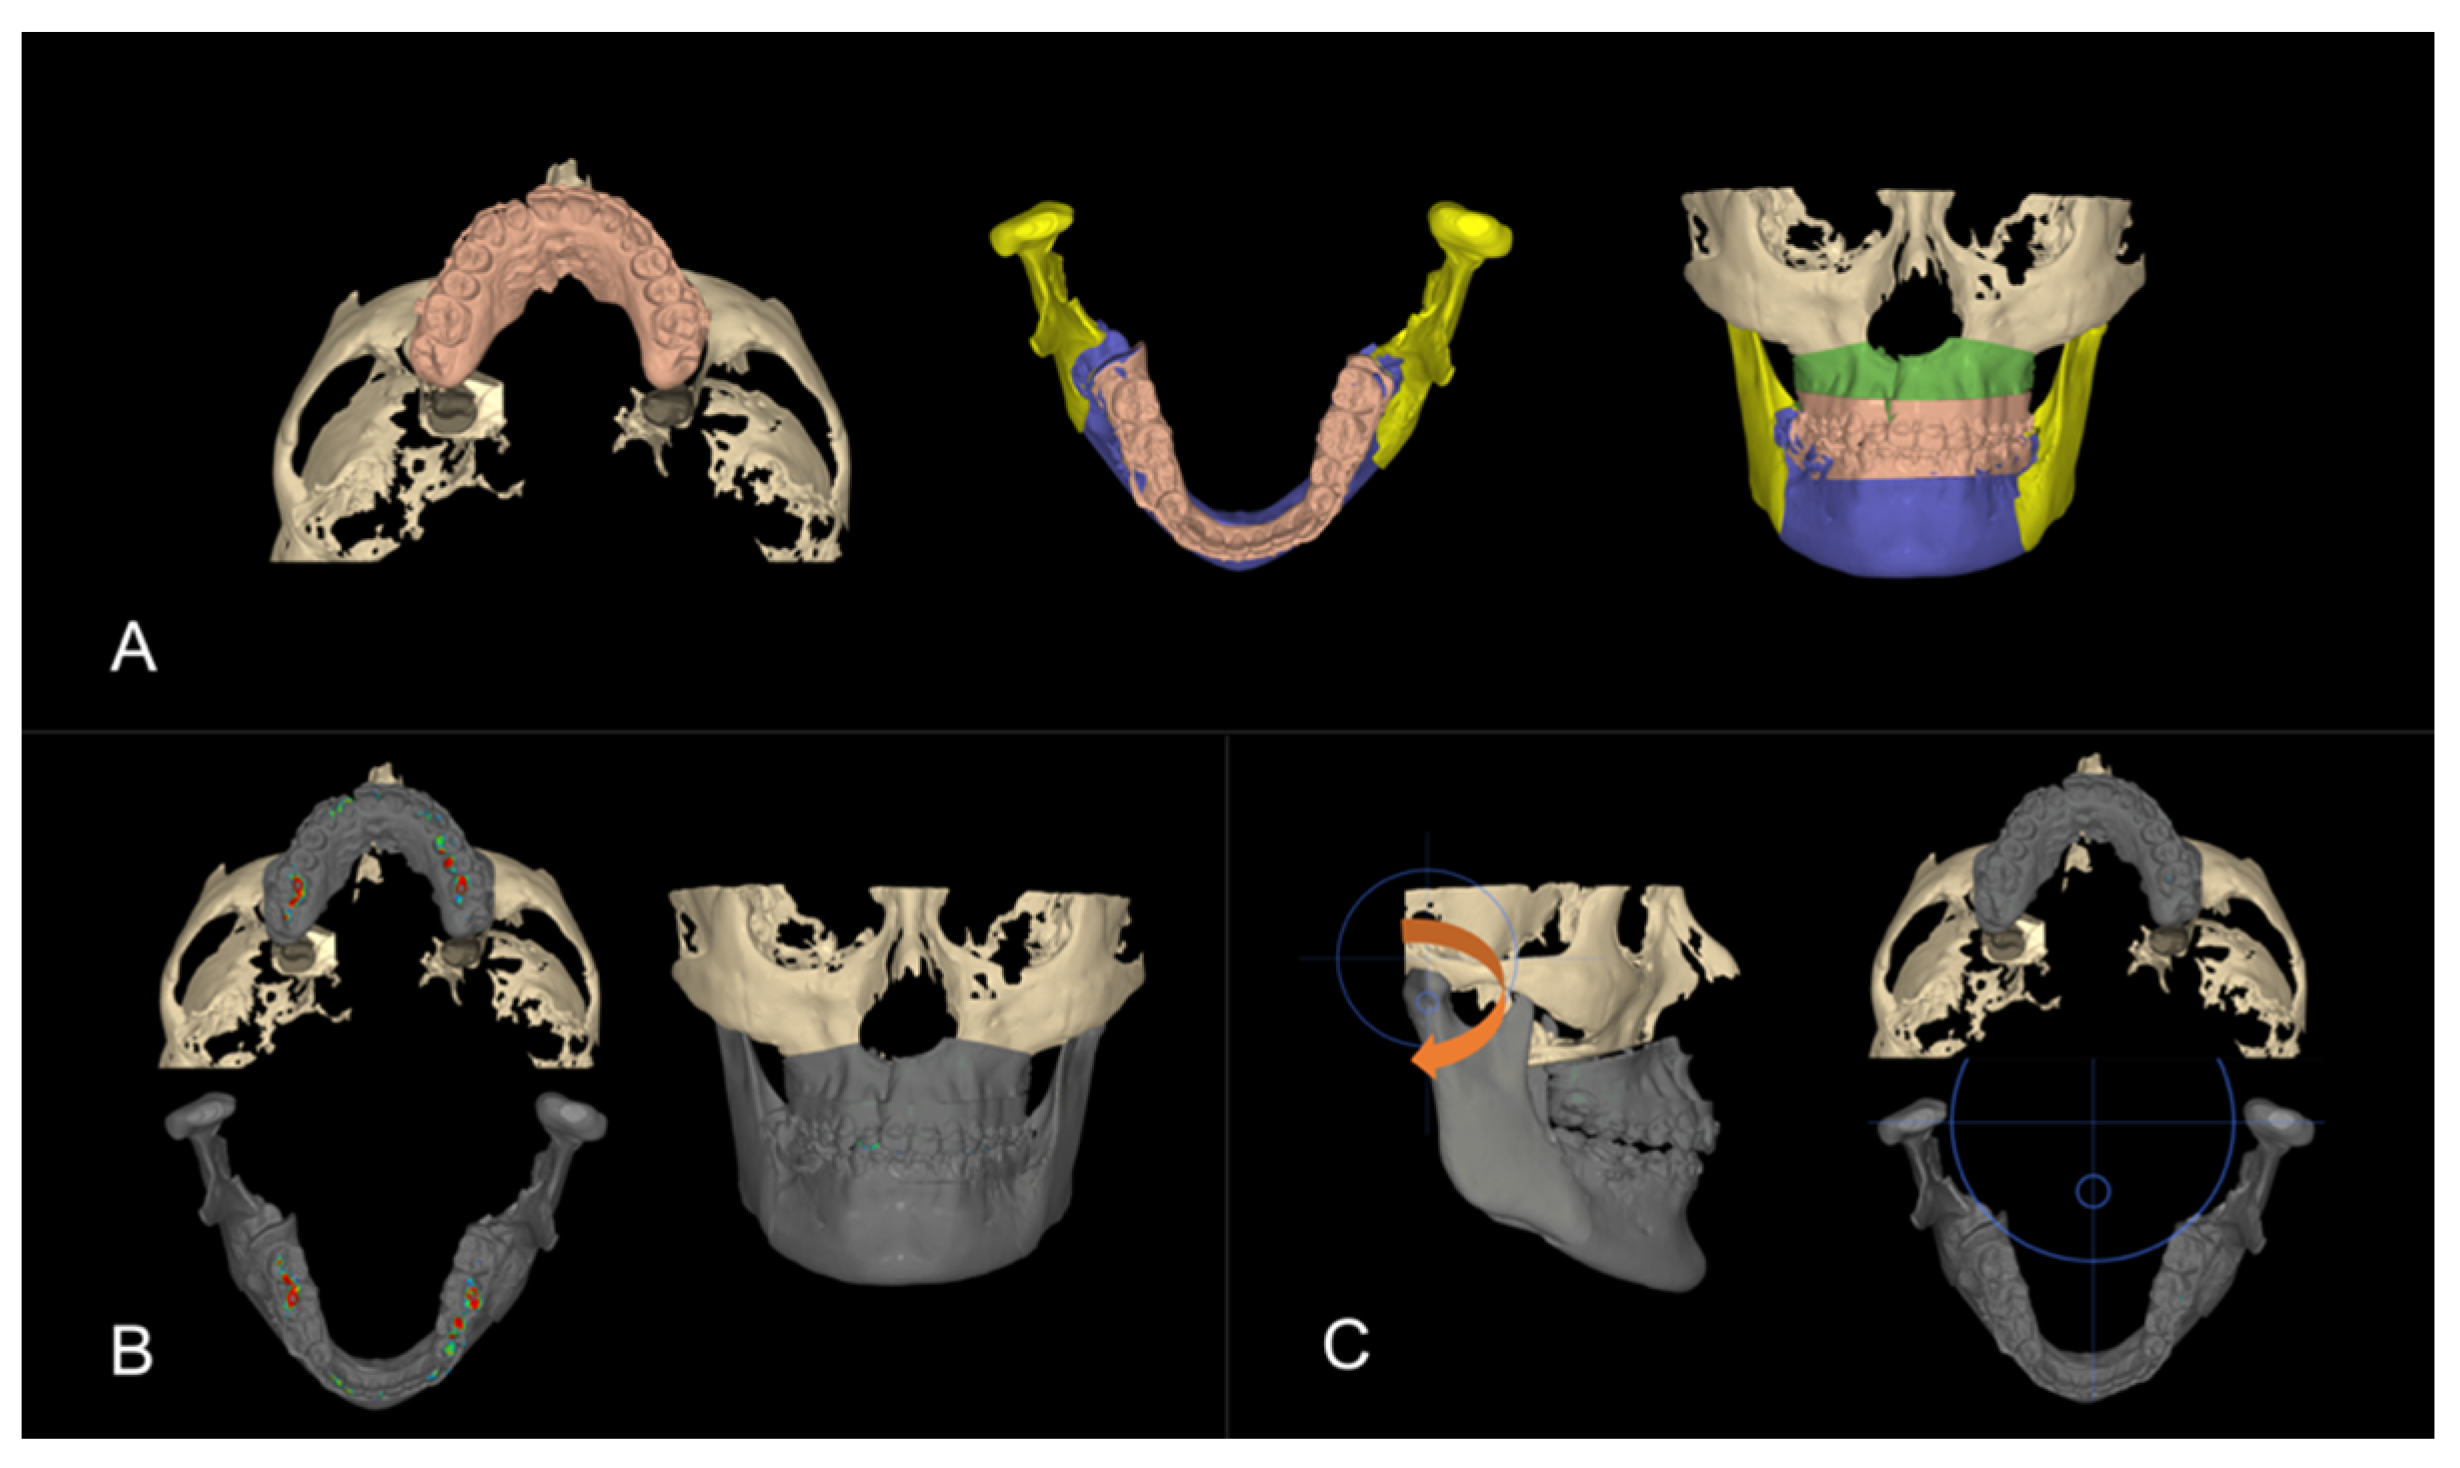

3.1. Step 1: Virtual Orthodontic Setup

3.2. Step 2: Virtual Surgical Repositioning

3.3. Step 3: Reverse Engineering the Transitional Occlusion